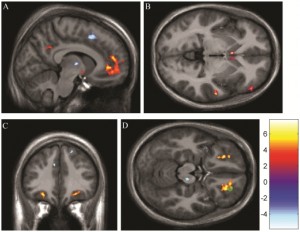

Tienen la hipótesis de que ver las fotos de la pareja sentimental será asociado con la activación neural en los centros de procesamiento de recompensa y puede reducir el dolor. En un estudio de resonancia magnética (fMRI), examinaron a 15 personas durante los primeros nueve meses de una nueva relación romántica.

Los participantes completaron tres tareas bajo periodos de dolor moderado y alto: ver fotos de su pareja, ver fotos de amigos y familiares en situaciones atractivas, y una tarea de distracción basada en palabras demostraron que puede reducirse el dolor.

La pareja y las tareas de distracción redujeron significativamente el reporte de dolor hecho por ellos mismos, aunque sólo la pareja quedó asociada a la activación de los sistemas de recompensa.

El resultado sugiere que la activación neural de los sistemas de recompensa por medios no farmacológicos puede reducir la experimentación del dolor.